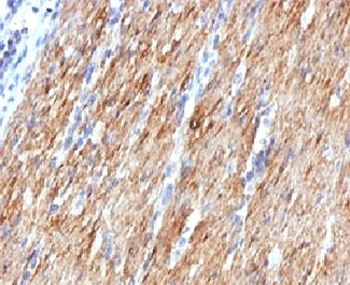

IHC: Formalin-fixed, paraffin-embedded human Leiomyosarcoma stained with SMMHC antibody (MYH11/923).